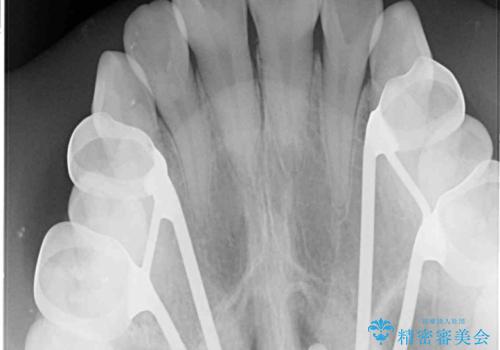

- 前歯の開咬と、受け口による咬み合わせの悪さを気にして来院された患者様です。

上顎歯列が狭窄していたため、急速拡大装置により上顎骨を側方に拡大し、その後ワイヤー装置にて矯正治療を行うこととしました。

舌の突出癖が開咬の原因であったので、改善のための舌トレーニングを行っていただきました。